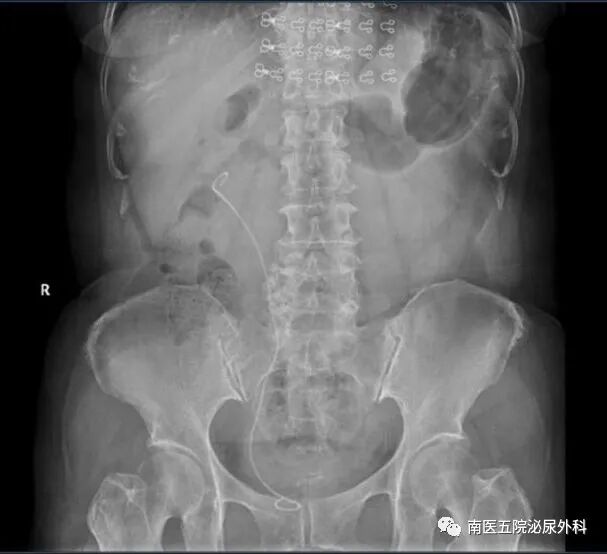

患者何某某,性别:女,年龄:57岁,入院时间:2023.8.17,患者主诉:右侧腰腹部疼痛伴肉眼血尿10天。诊断:右肾多发结石并右肾积液。术式:经尿道钬激光输尿管软镜碎石取石术。

术前影像检查

术后复查,结石已全部清除